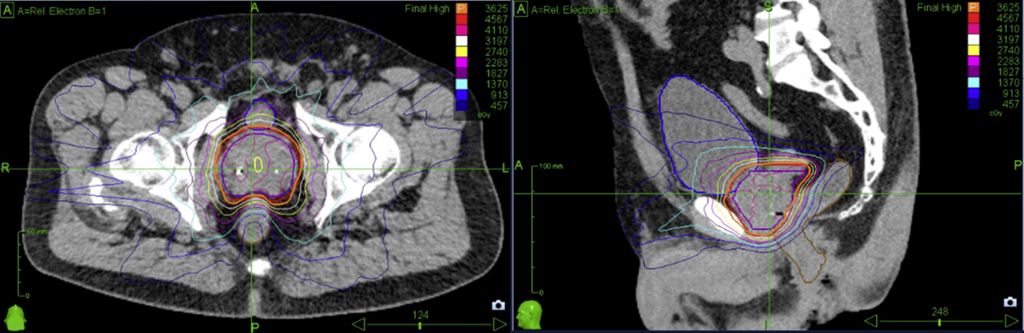

Fig. 1: Dose distribution for prostate cancer patients treated on robotic SBRT platform (Cyberknife)